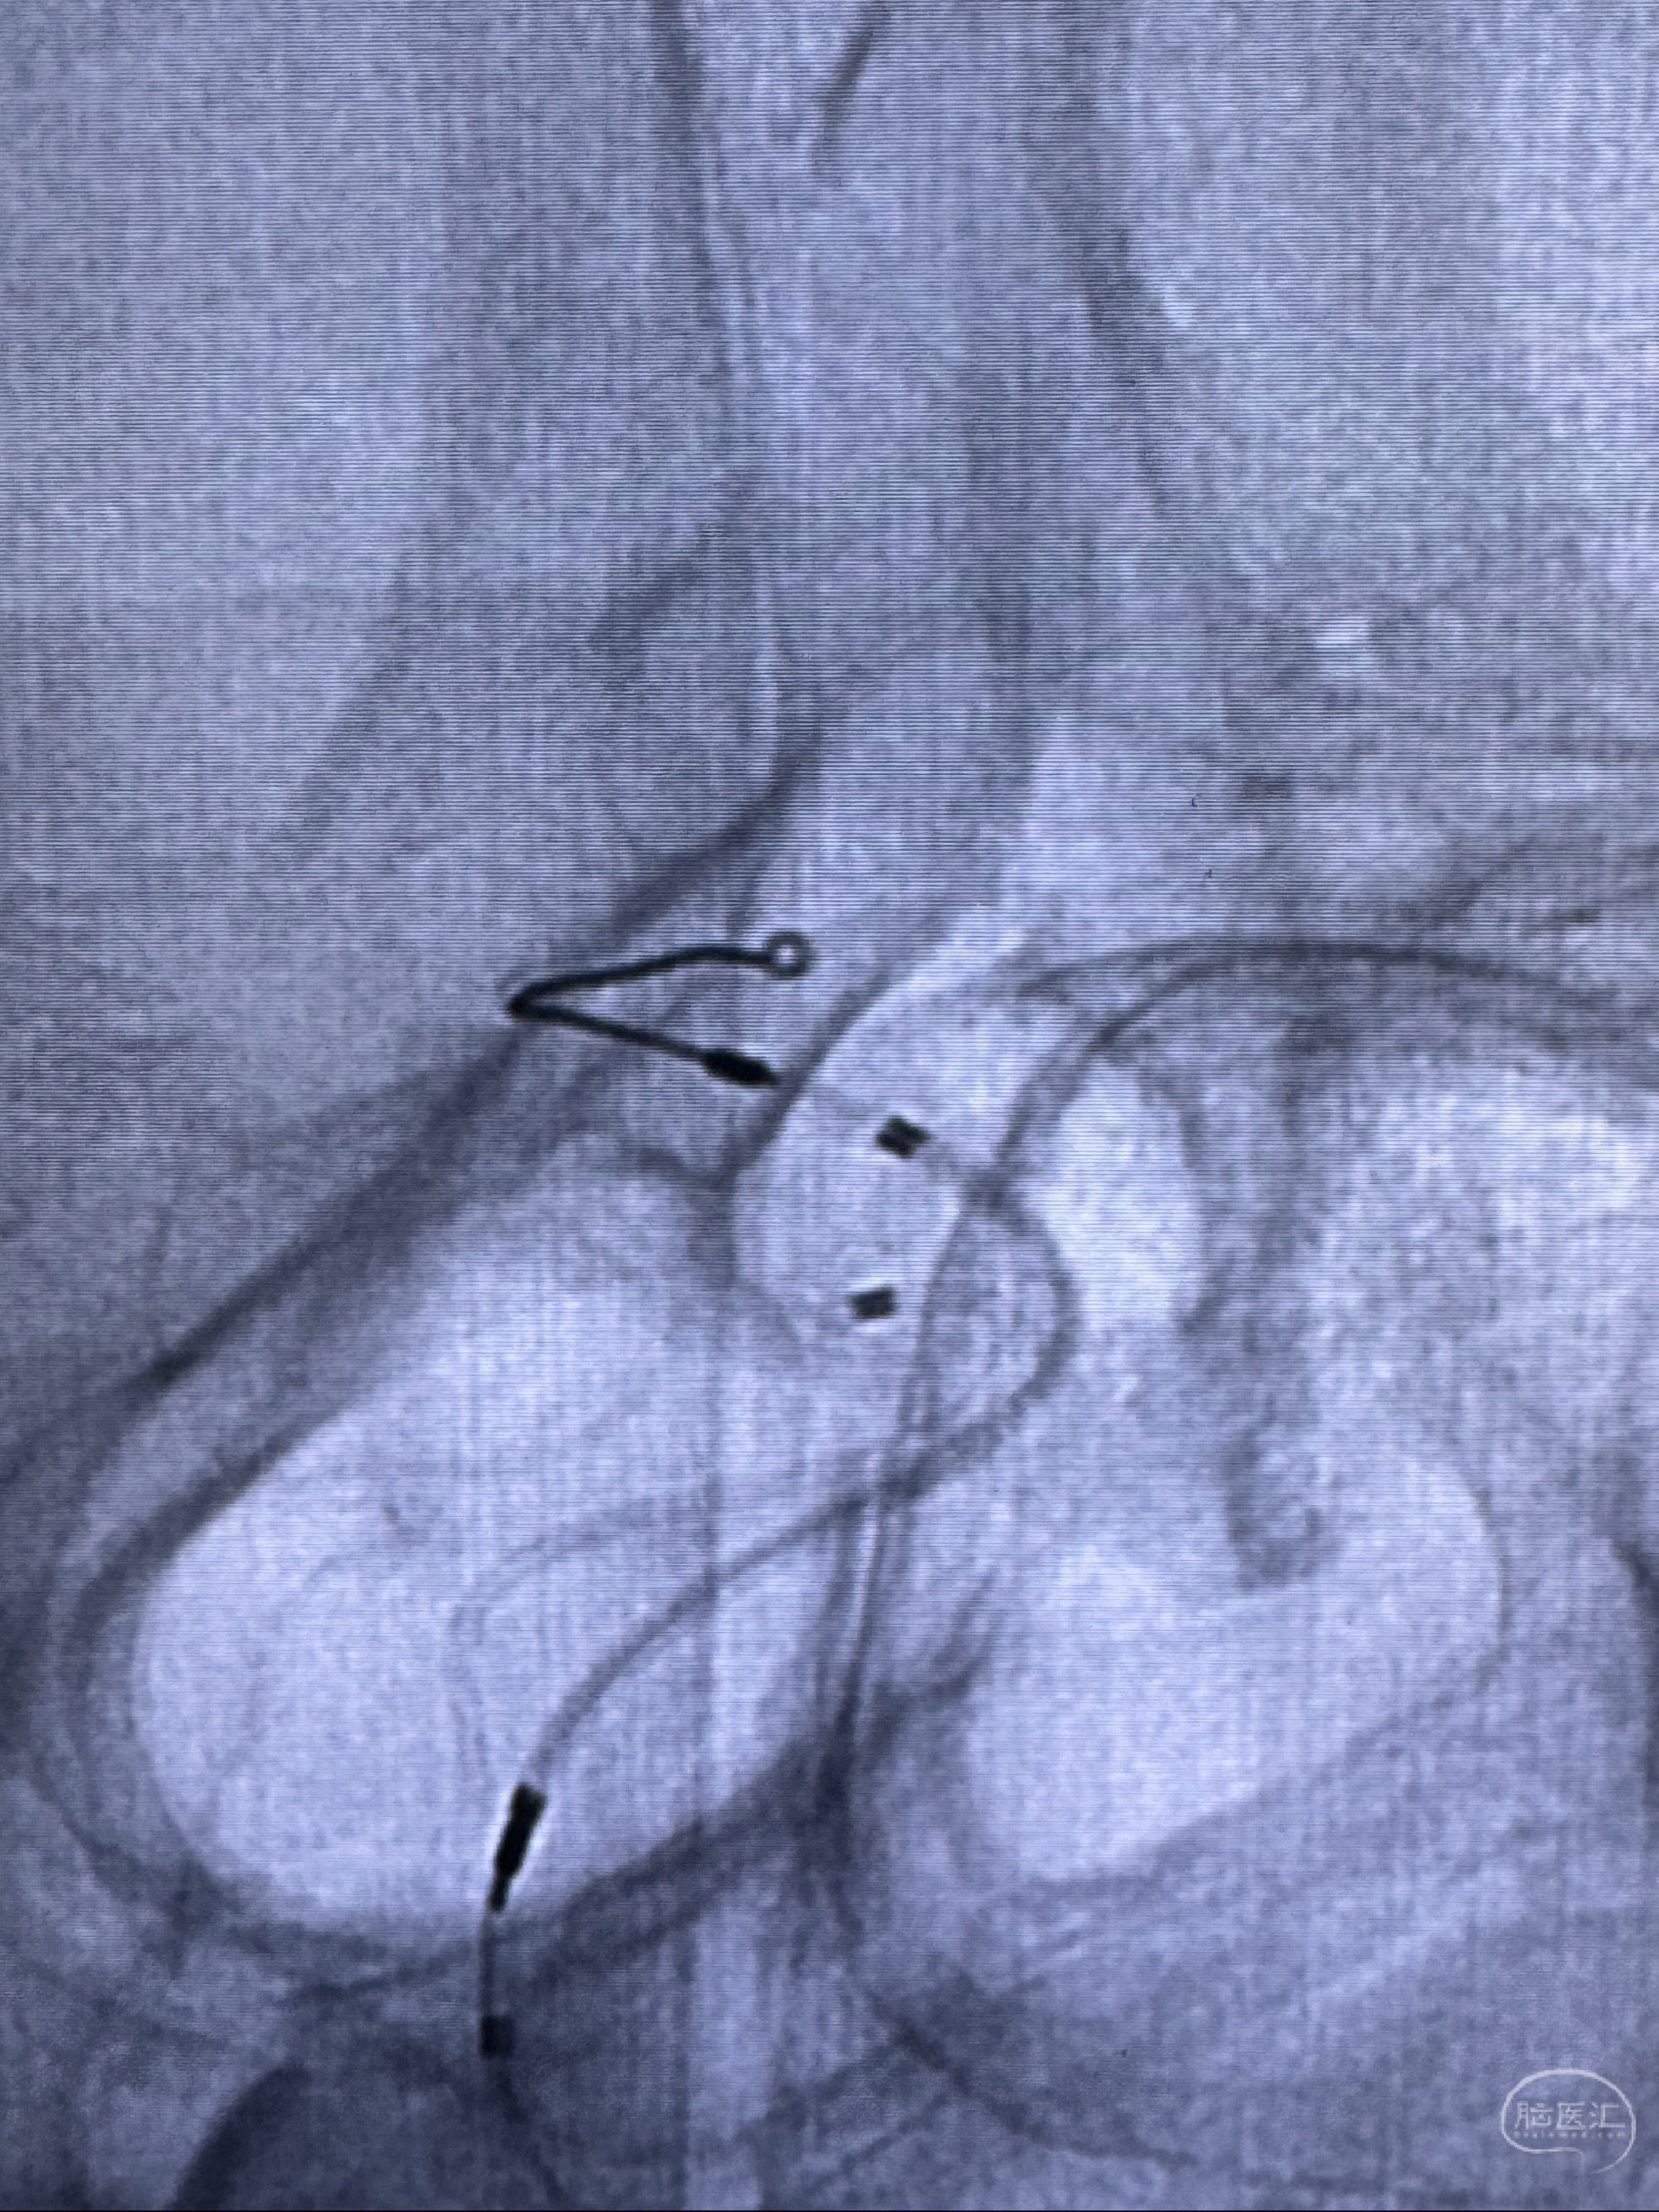

2023-11-29全麻下行NeuroformEZ4.5-20mm支架辅助栓塞

麻醉苏醒佳,遵嘱动作

术后即刻CT